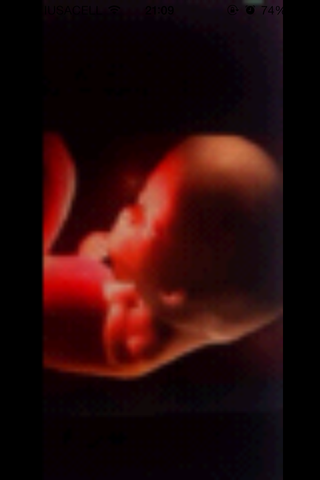

El embrido se convierte en feto

Los tejidos y órganos maduran:

El esqueleto se va formando

Él bebe mide 1 cm aproximadamente